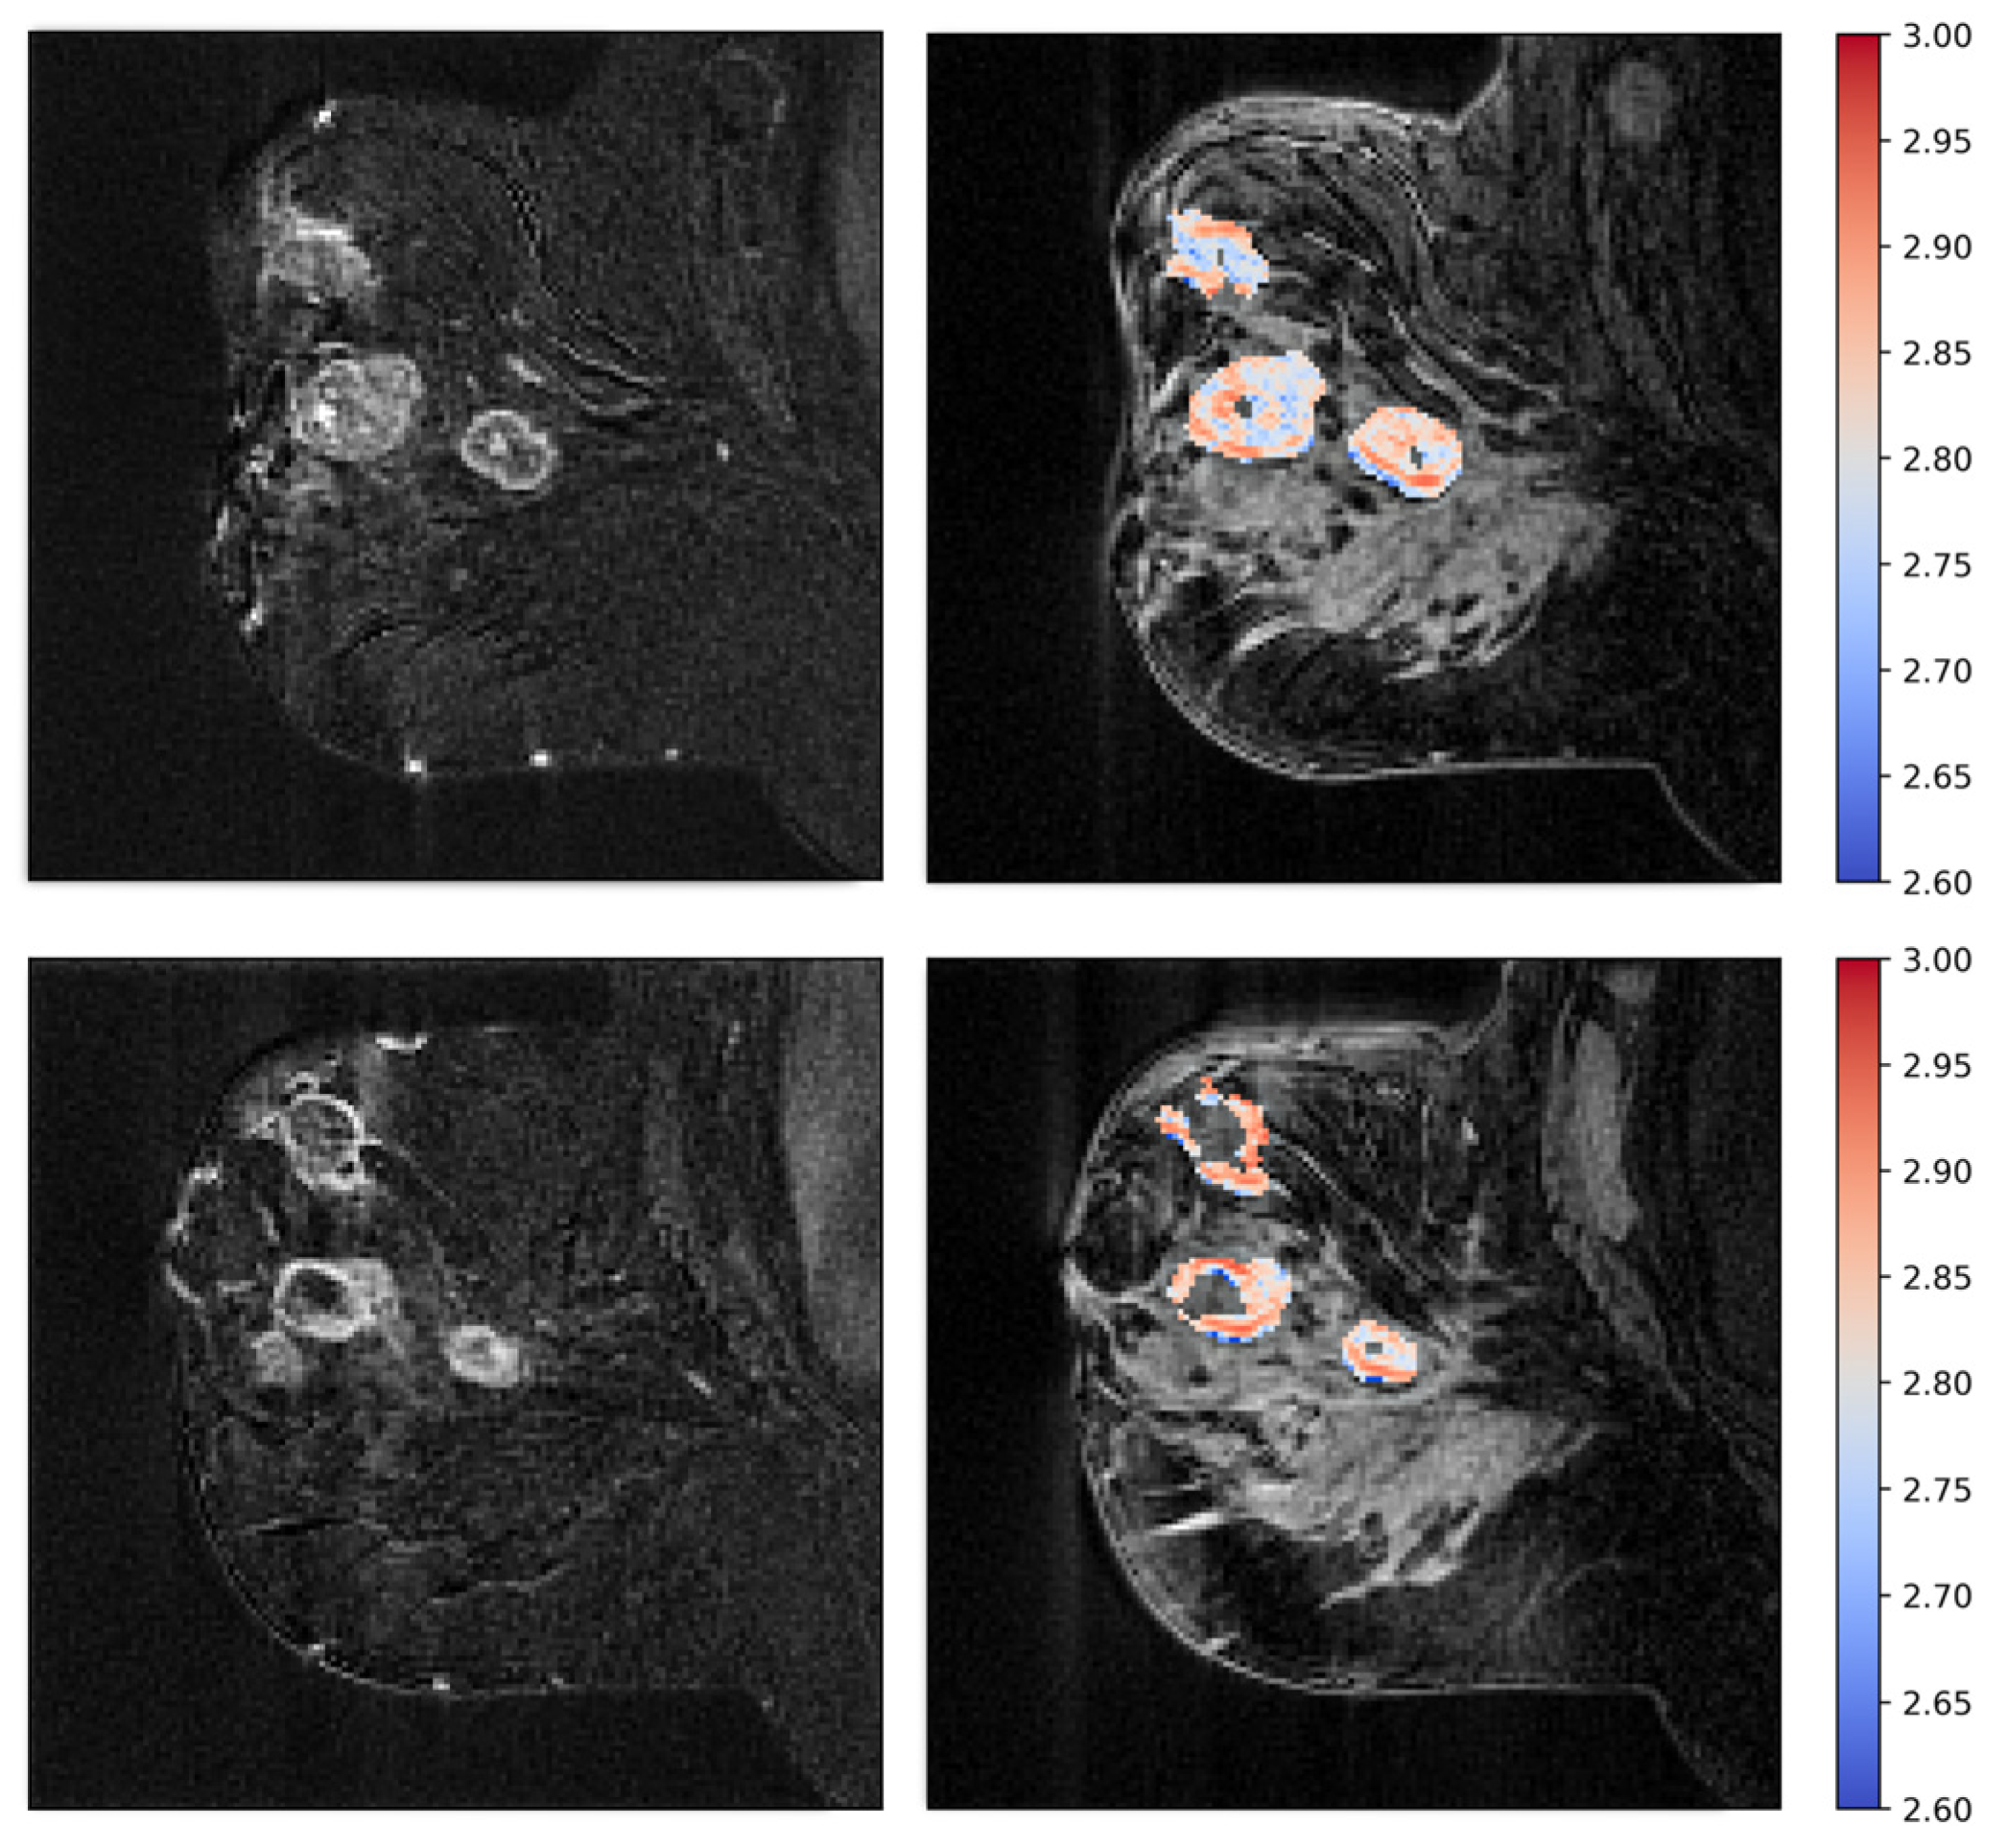

2.6. Tumor Vascular Architecture—Texture Analyses

3.3. Tumor Vascular Architecture